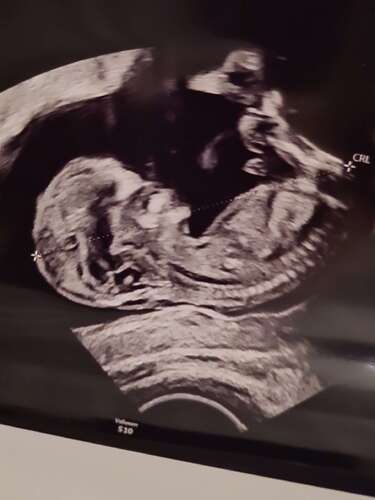

Niet de beste kwaliteit foto’s omdat ik zelf even een echo heb gemaakt tijdens m’n werk als SEH-arts ;-) (kwaliteit van apparaat is ook niet voor obstetrie echo’s). Anders volgen over 2 dagen betere echo’s!

(Ik zie dat ik op de verkeerde post heb gereageerd net, je vroeg om meer foto’s- bij deze. )

Allerlaatste dan!

Hoopte al dat jij zou reageren! Volgens de echoscopiste kon je de nub hier niet zien. Zie jij hem wel?